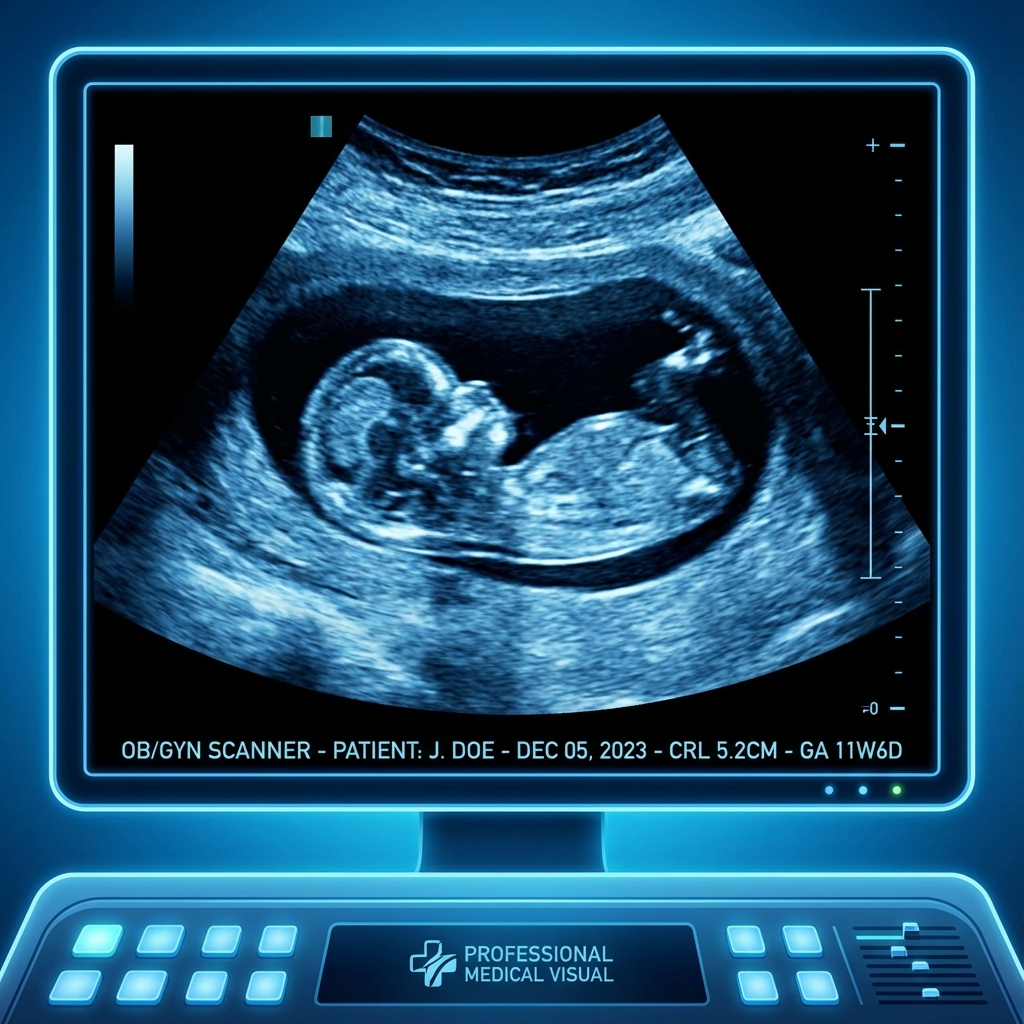

Fetal Ultrasound Scan

2. The NT Scan (11-13 Weeks)

This is the time for serious thinking. The Nuchal Translucency (NT) Scan assesses the risk of common genetic problems that can cause irreversible mental retardation and other structural malformations.